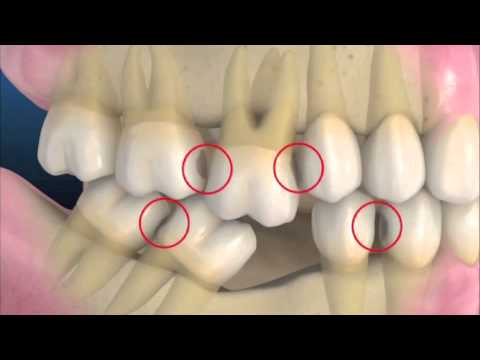

缺牙會使牙齒位移,造成咬合位置改變

在全口重建的治療中,其精隨在於如何建立新的牙齒外型、新的咬合關係和新的咬合高度。因為咬合高度的喪失是經年累月所造成的,所以在全口重建的過程中,病人的適應性和耐心是絕對需要的。